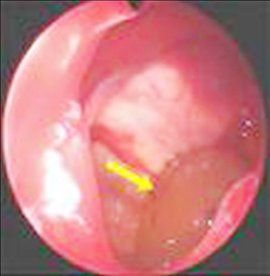

3.鼻腔檢查:鼻腔外側壁向中線移位。

6、鼻竇囊腫患者鼻腔外側壁向中線移位。